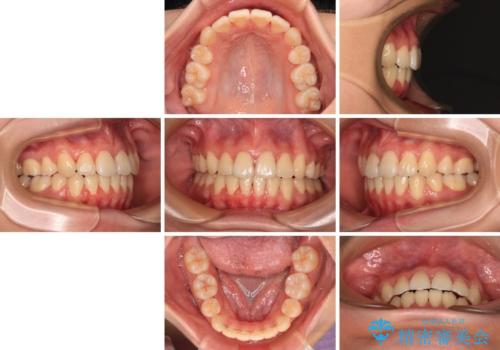

- メタルブラケット

- 1年6ヶ月

- 抜歯矯正の後戻りを気にして来院された患者様です。

舌の突出癖によるオープンバイトになっていたため、インビザラインによるマウスピース矯正をおすすめしましたが、自己管理の自信がないとのことで、ワイヤー装置による矯正治療を行うこととしました。

舌の突出癖が認められると、上下前歯の隙間を閉じることができません。

舌のトレーニングをしっかりと行っていただくことで、歯列を整えることができます。